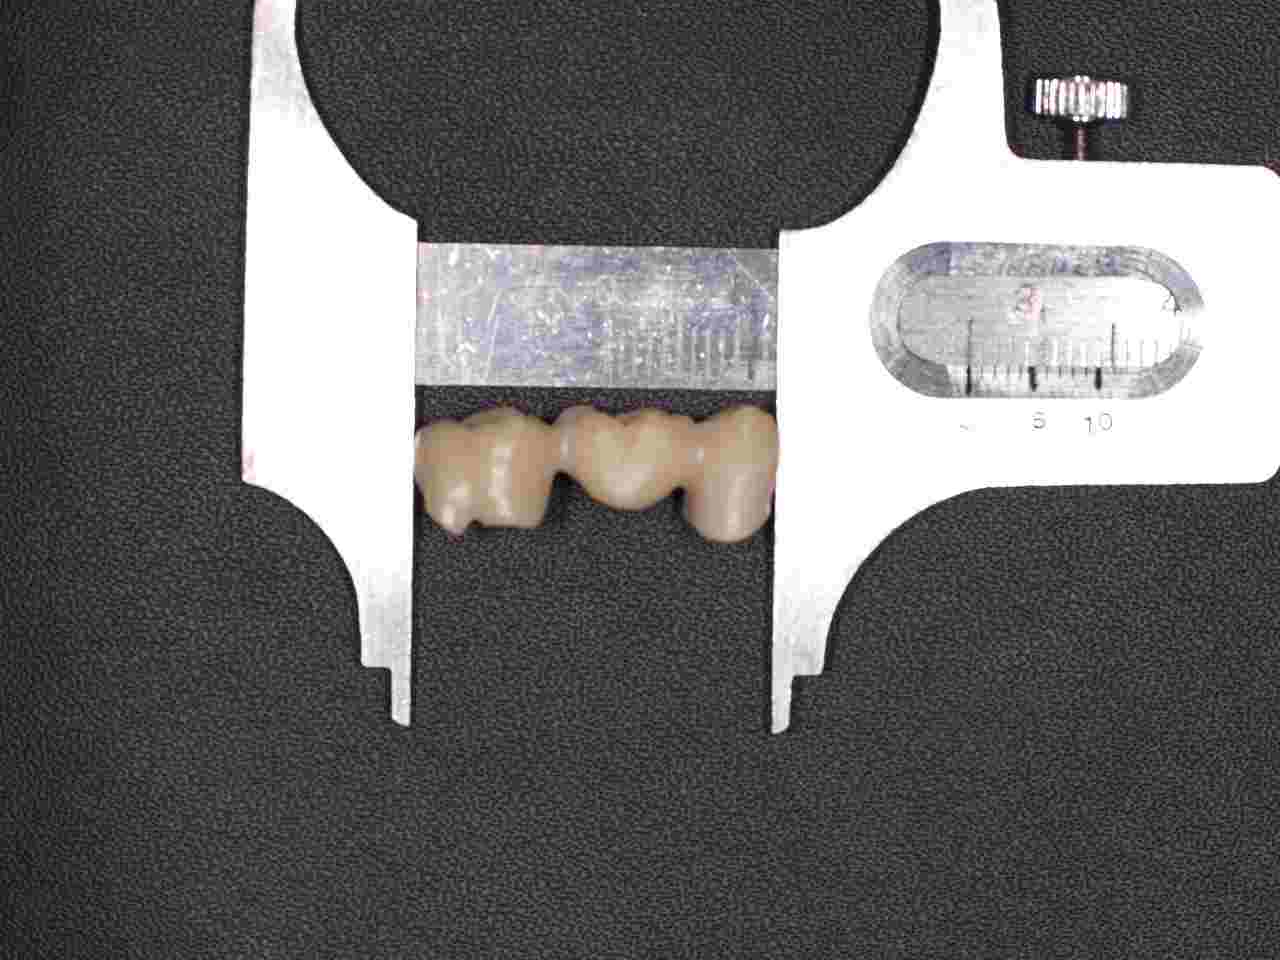

ジルコニアフレームを使用したジルコニアブリッジも6歯程度まででそれ以上になると従来通りのメタルボンドに切り替えるようにしています。 ワンピースではフレイムの適合、制度が落ちる為郎着作業が必要となりジルコニアは蝋着ができないことが理由に挙げられます。|お知らせ |広島市安佐南区の歯科医院

ジルコニアフレームを使用したジルコニアブリッジも6歯程度まででそれ以上になると従来通りのメタルボンドに切り替えるようにしています。 ワンピースではフレイムの適合、制度が落ちる為郎着作業が必要となりジルコニアは蝋着ができないことが理由に挙げられます。

ジルコニアフレームを使用したジルコニアブリッジも6歯程度まででそれ以上になると従来通りのメタルボンドに切り替えるようにしています。 ワンピースではフレイムの適合、制度が落ちる為郎着作業が必要となりジルコニアは蝋着ができないことが理由に挙げられます。